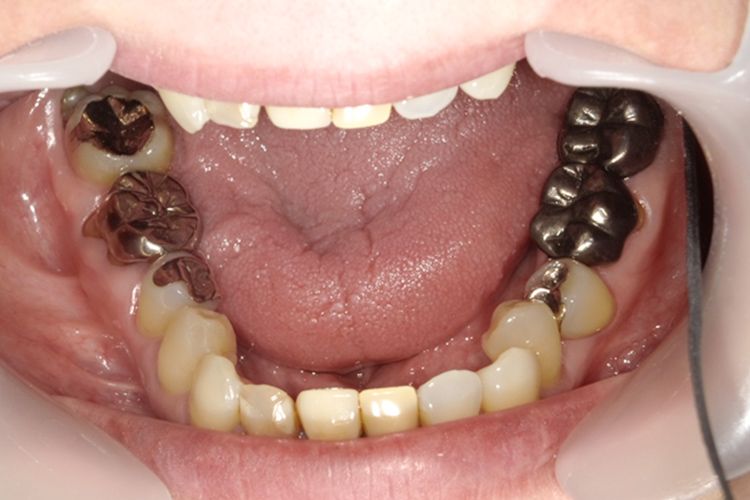

成人上顎拡大装置

| 費用 | 165,000円 |

|---|---|

| 治療期間 | 約1ヶ月~3ヶ月 |

| メリット |

歯列を広げられるので便宜抜歯するリスクを回避できる。 歯列だけではなく、顎の骨格も改善できるので、口呼吸から鼻呼吸へ改善される可能性が高い。 装置が目立たない。 |

| デメリット | 使用できる症例が限られるが治療期間が長く、装置を装着している間は、装置周辺に付着する食べ物をしっかりと取り除く必要がある。 |

矯正前

拡大装置

拡大後

ブラケット

矯正後